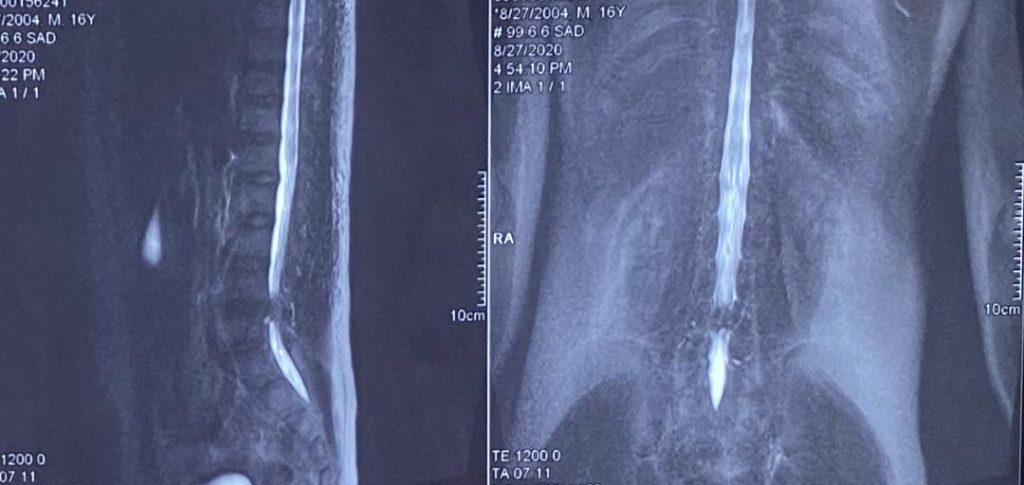

تصاویر قبل ار جراحی

پارگی دیسک و آسیب مفصل فاست L4-L5 وجود داشت که عمل جراحی میکروسکوپیک فنستراسیون و دیسککتومی دوطرفه انجام شد.